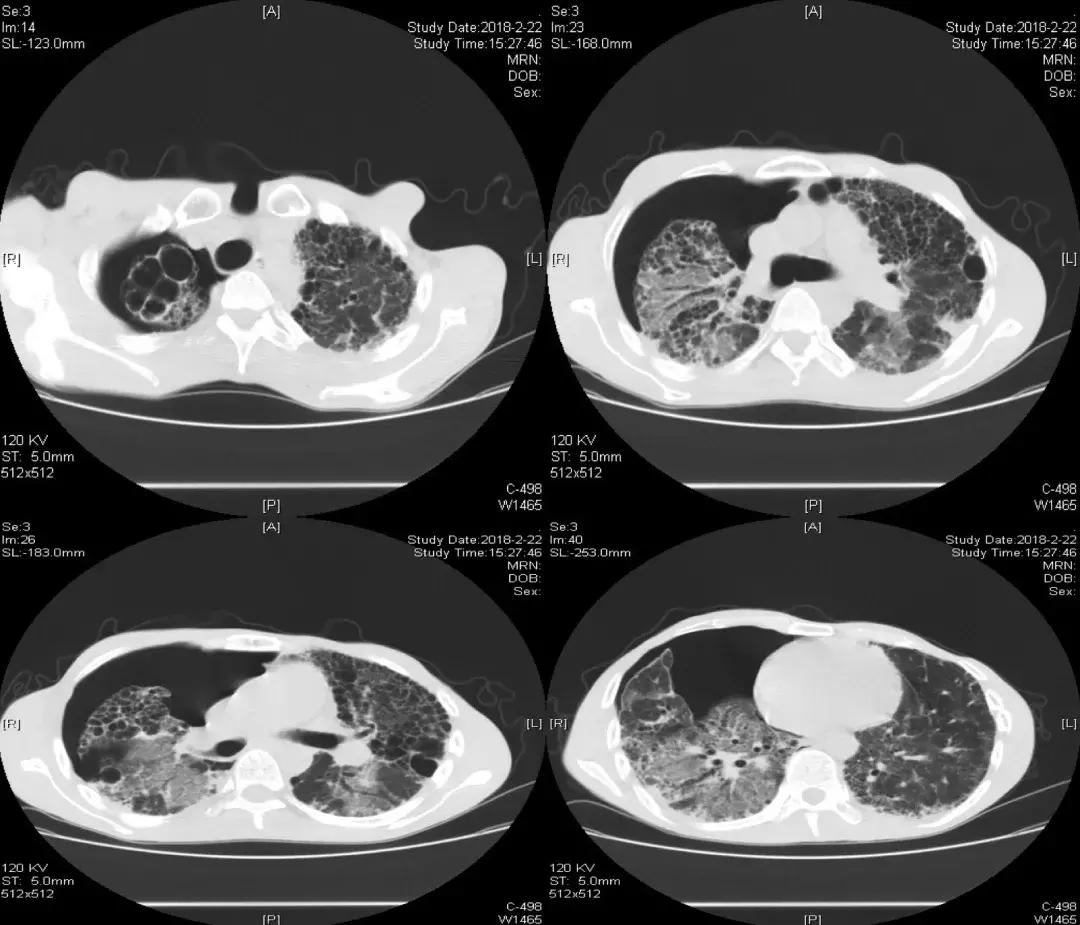

胸部CT:双肺胸膜下见斑片状磨玻璃影、模糊小结节灶及纤维网格状影,似乎和我们常见的肺纤维化IPF不太一样,以双上肺为主。右下肺外基底段片状影,边界模糊,局部支气管略显增宽(本院,2013-10-12)。

2014-02-21(入院第2天)胸部CT:

发现与2013-10-12胸部CT相似,主要还是以双上肺和胸膜下为主的网格状影,其次右下肺有片状影,可看到充气支气管征。